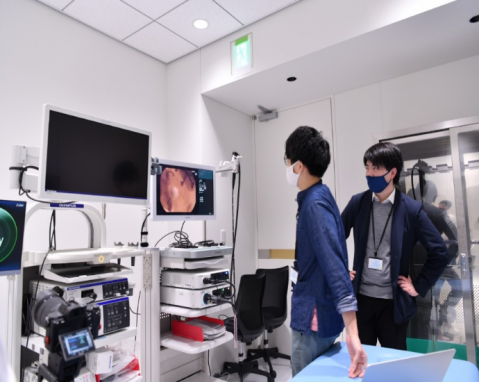

加藤さん:メイン事業は、内視鏡検査におけるAI診断支援ソフトウェア事業です。100を超える共同研究施設より医療データを収集し、胃がんの見逃しを減らすことを目標とした診断支援ソフトウェアの研究開発を行っています。第1弾の製品は2022年には承認を得て販売を開始する予定です。

▼AIで医療現場の課題を解決し、診療を変える

加藤さん:プロトタイプに対してヒアリングをさせていただいたり、実際現場で使っていただいたりするのですが、リアルなご感想やご意見をいただくとやりがいを感じますし、応援のお言葉や「早く出してほしい」というお声はモチベーションになります。早く内視鏡AIが医療現場で活躍する未来を作りたいです。 医療業界では、さまざまな規制や法律に準拠して製品開発を行う必要があります。規制に目を向けると堅苦しい側面がありますが、良いものを社会に届けるプロジェクトに取り組んでいるということ自体がやりがいです。社会貢献性の高い事業を手掛けているという思いのもと、日々の業務に取り組んでいます。